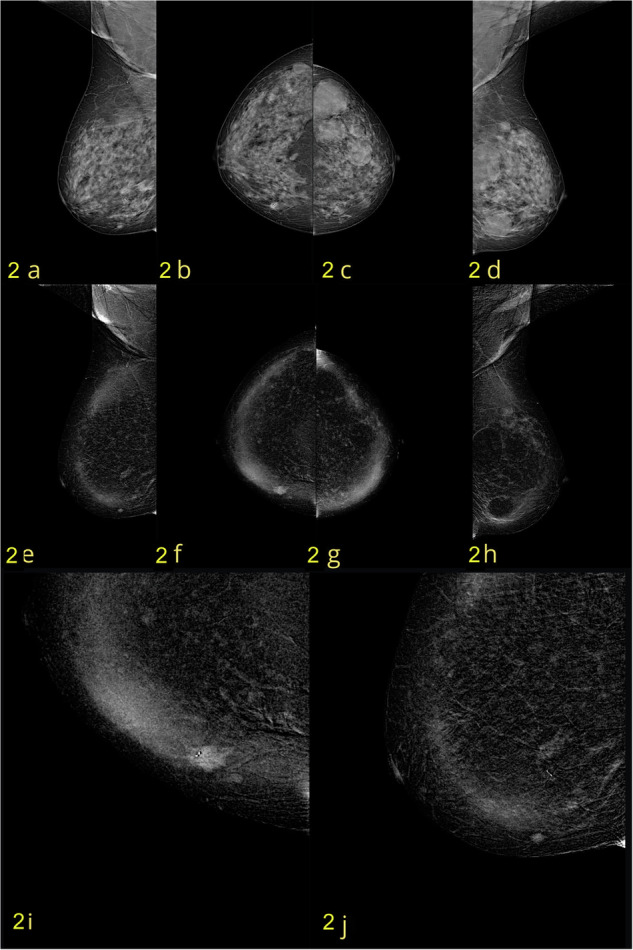

Methods: This two-center retrospective study included 205 patients who underwent CEM between March 2021 and February 2022. Patients were injected with HCCM at 1.0 mL/kg bodyweight at an IDR of 1.2 gL/s. Standard cranio-caudal and mediolateral-oblique views were acquired. Images were reviewed independently by two experienced radiologists who were blinded to patient clinical and imaging information. Diagnostic performance, including sensitivity, specificity, and accuracy, was assessed based on histological or long-term imaging follow-up as the reference standard.

Results: Among the 205 patients, 149 (72.7%) had malignant lesions, and 56 (27.3%) had benign findings. The sensitivity and specificity of CEM were 96-97% and 84-87.5%, respectively, with an overall accuracy of 93-95%. The IDR achieved with HCCM resulted in excellent contrast enhancement, particularly in patients with aggressive malignancies. ROC analysis confirmed the good diagnostic performance, with AUC values of 0.90-0.92. Compared to conventional mammography and ultrasound, CEM demonstrated significantly higher diagnostic accuracy, especially in patients with dense breast tissue.